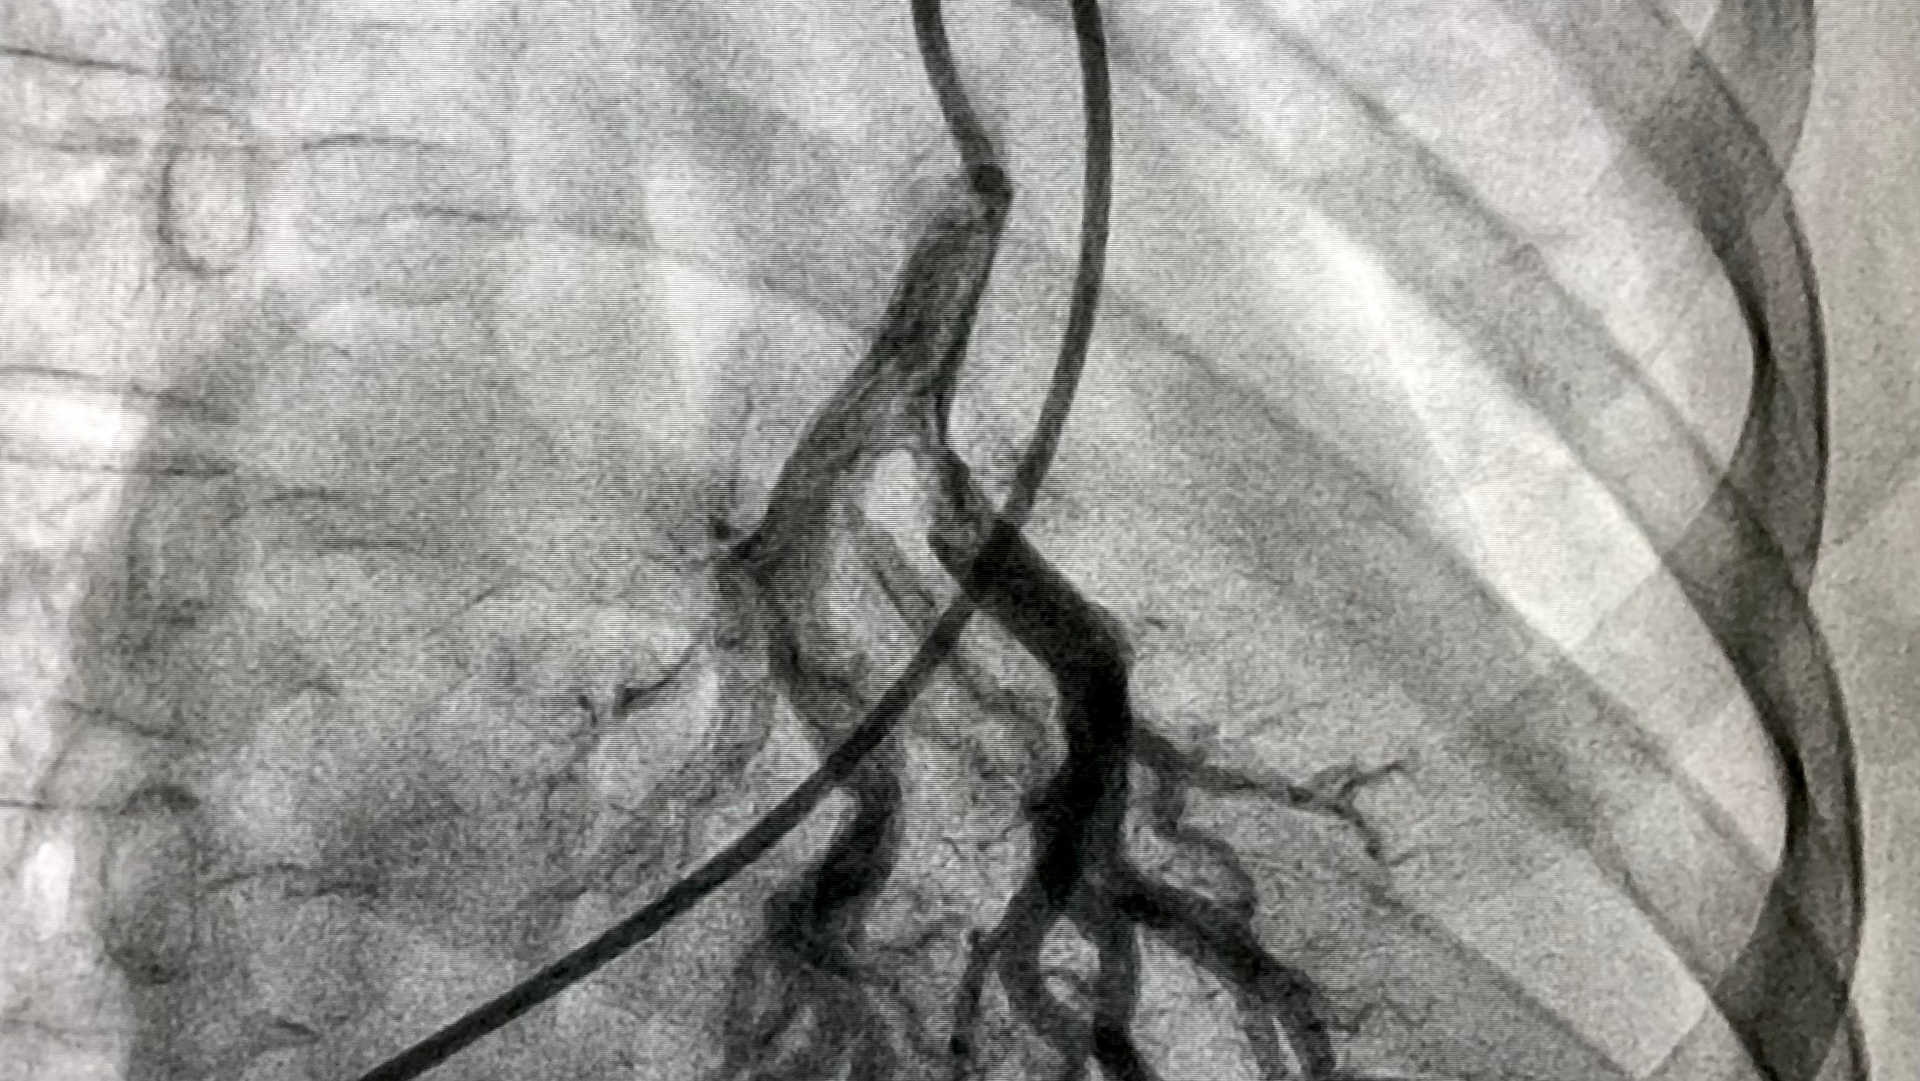

- Ultrasound-facilitated catheter-directed fibrinolysis with the EkoSonic system plus anticoagulation.

- Alteplase regimen: 2 mg bolus per catheter, then 1 mg/hour per catheter for 7 hours; total 9 mg for unilateral treatment or 18 mg for bilateral treatment.

- Bilateral proximal thrombus generally prompted bilateral catheter placement.